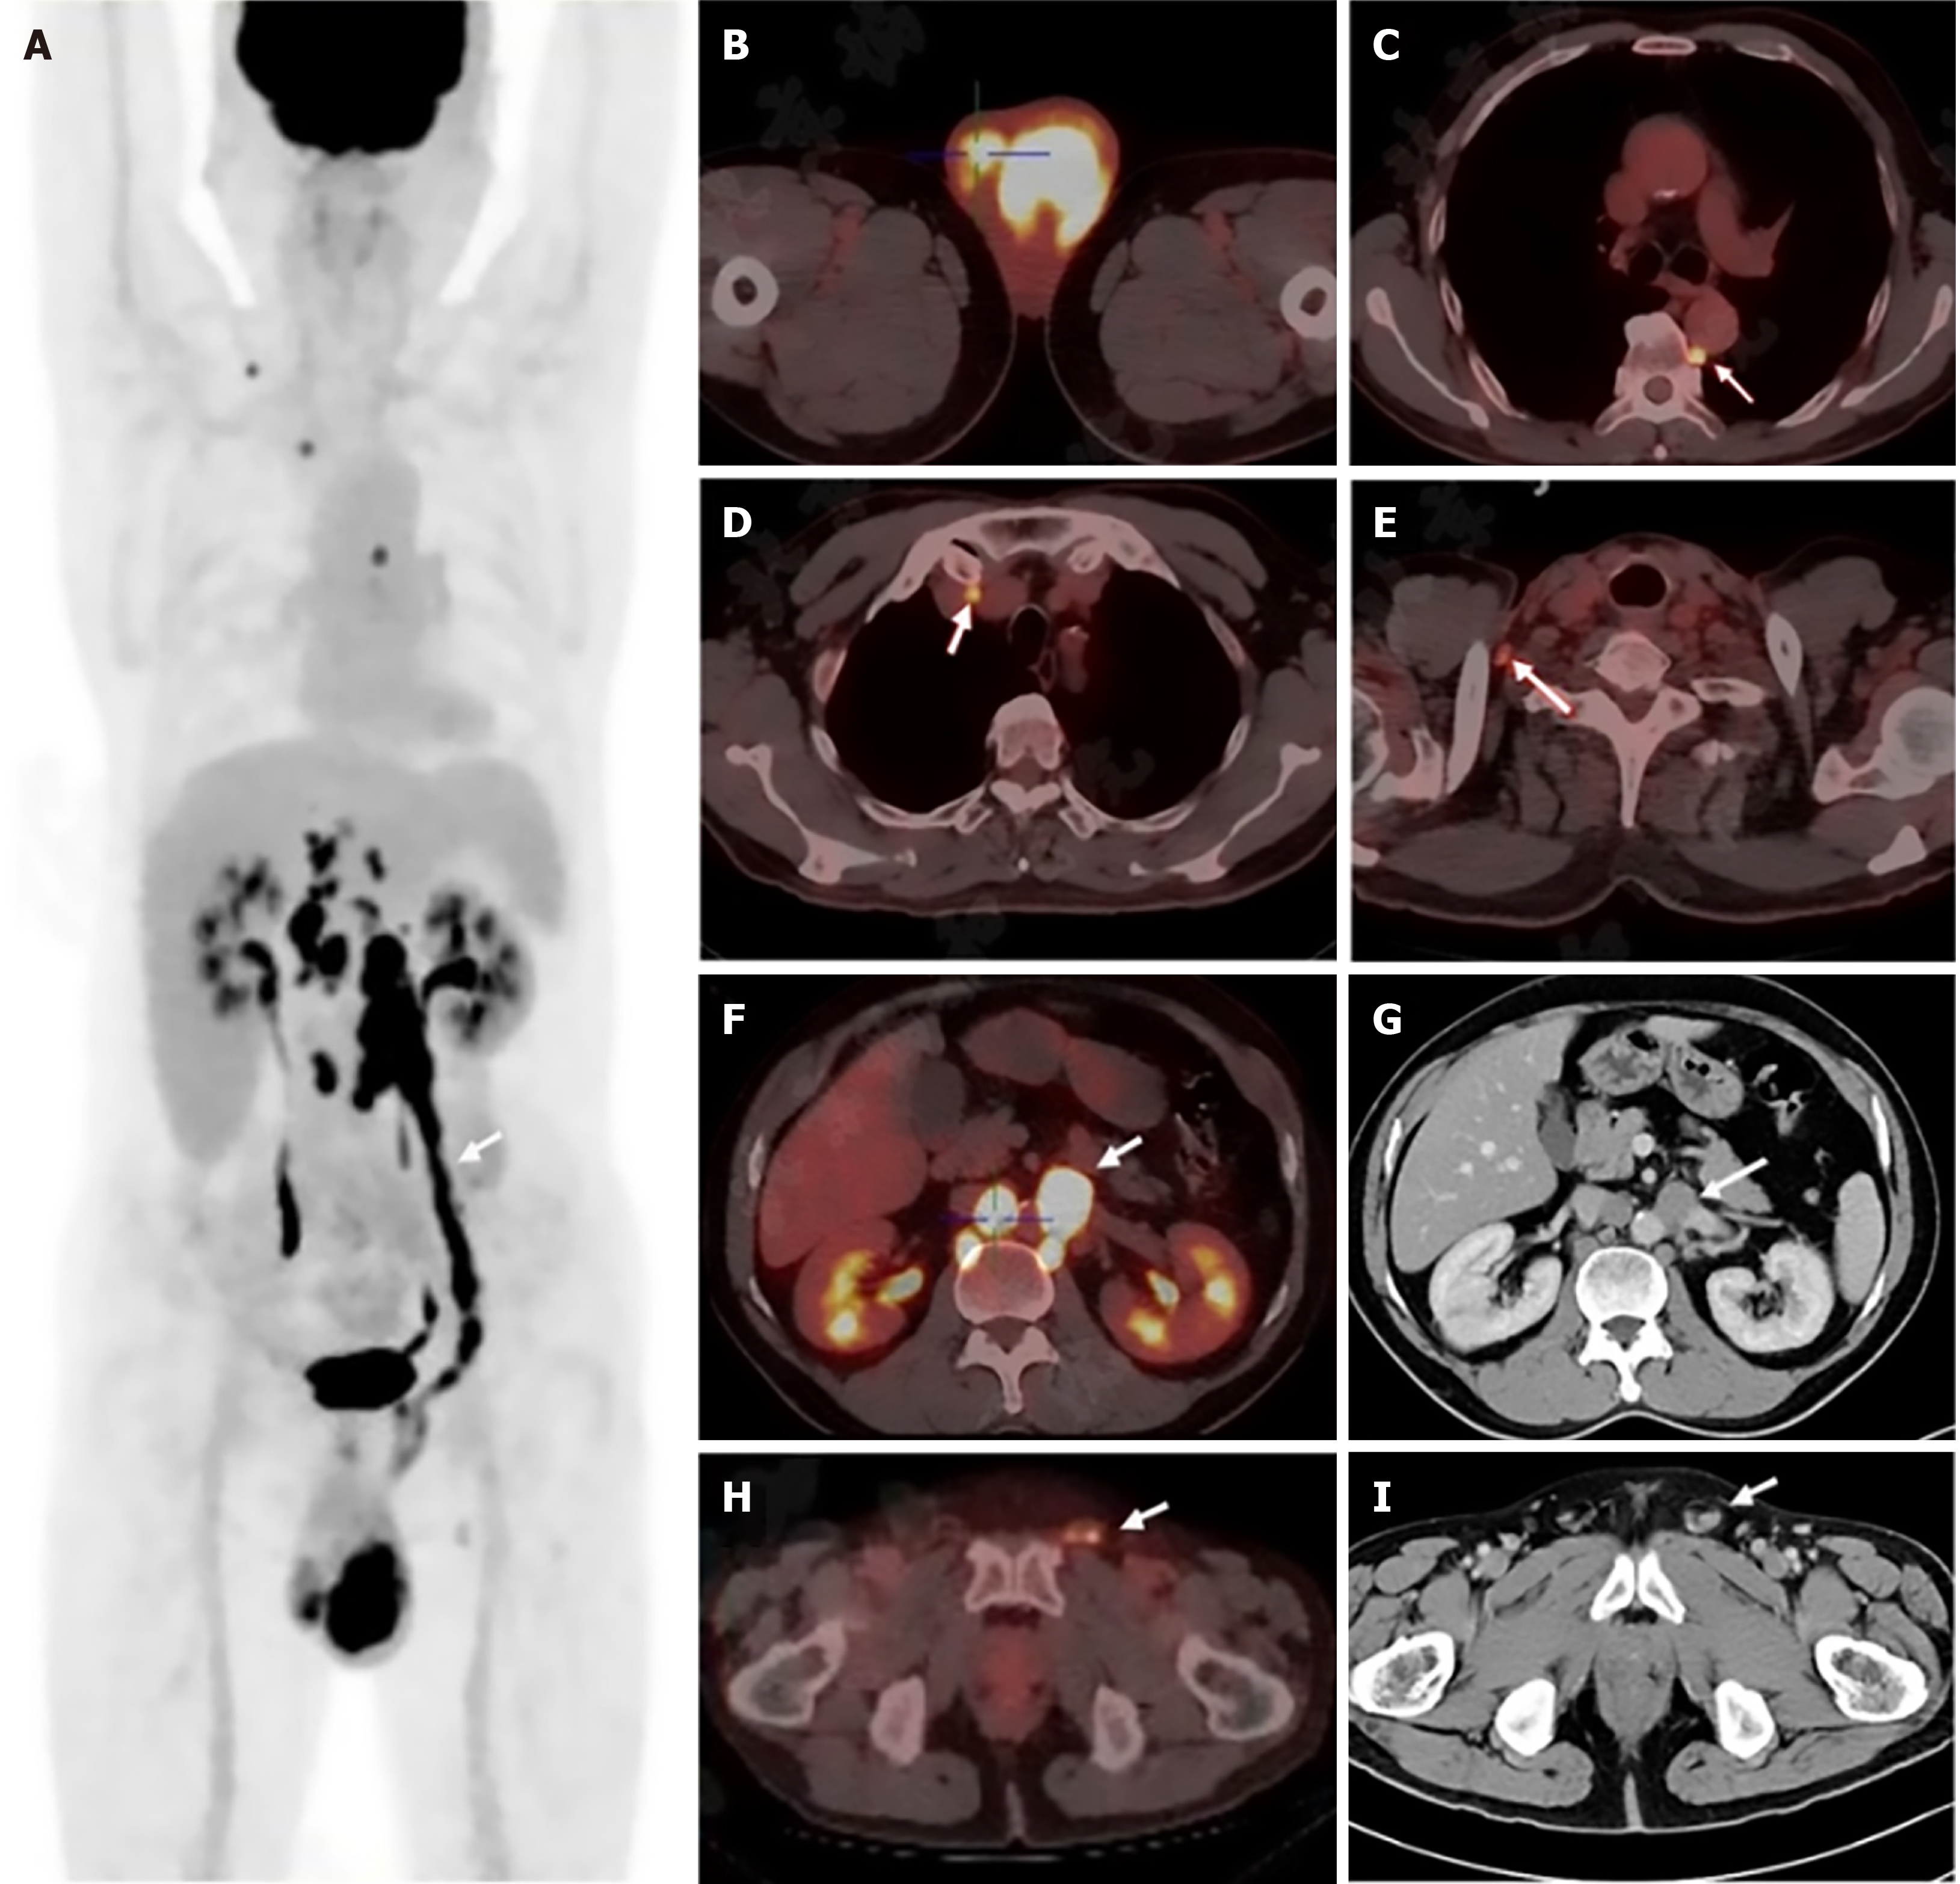

Figure 1 18F-fluorodeoxyglucose positron emission tomography/computed tomography and contrast-enhanced computed tomography images.

A: Linear uptake along the left gonadal vein (arrow, SUVmax 16.5); B: Bilateral testicular lesions (left: SUVmax 14.1; right: SUVmax 5.0); C: Paravertebral lymph node uptake (arrow); D: Mediastinal lymph node uptake (arrow); E: Right supraclavicular lymph node uptake (arrow); F and G: Tumor thrombus in the left gonadal vein near the left renal vein (arrow); H and I: Tumor thrombus in the left spermatic cord (arrow).